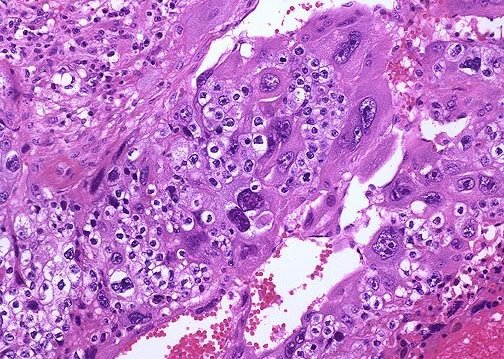

- Τα ιστολογικά ευρήματα: Μικρό οζίδιο αιμορραγικό με γκριζωπό-λευκό όγκο στην περιφέρεια. Η ιστολογική εξέταση δείχνει ότι το χοριοκαρκίνωμα περιέχει τόσο συγκυτιοτροφοβλαστικά όσο και τροφοβλαστικά κύτταρα. Τα συγκυτιοτροφοβλαστικά κύτταρα είναι υπεύθυνα για την παραγωγή της β χοριακής γοναδοτροπίνης.